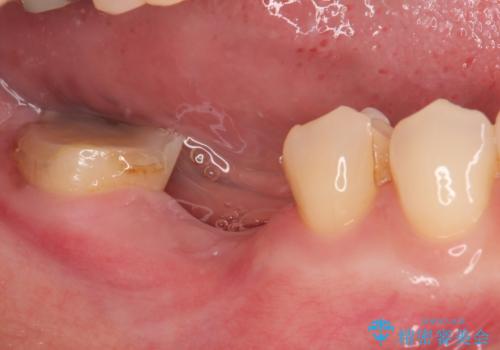

クラウンを外したところ、目視でも確認できる破折線が認められたため、抜歯することとしました。

抜歯後も膿の出口が消えず、一番奥の歯を診察したところ神経組織の反応がなかったため、根管治療を行うこととしました。

再度の歯を根管治療したため、抜歯した部位の補綴治療は、強度の問題からブリッジよりもインプラントをおすすめしましたが、患者様希望によりブリッジを選択しました。